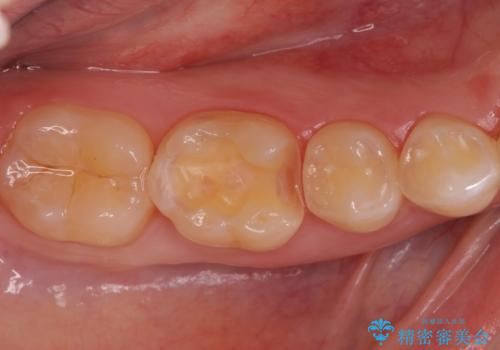

矯正後の虫歯治療 セラミックインレーでの治療

- 矯正後の虫歯治療です。

咬む面と歯と歯の間の虫歯に対してセラミックインレーでの修復処置をしていきます。

- 右下6 セラミックインレー 77,000円費用は治療当時の料金となります

下の奥歯は外から見える場所です。審美的なセラミックでの治療をおすすめします。